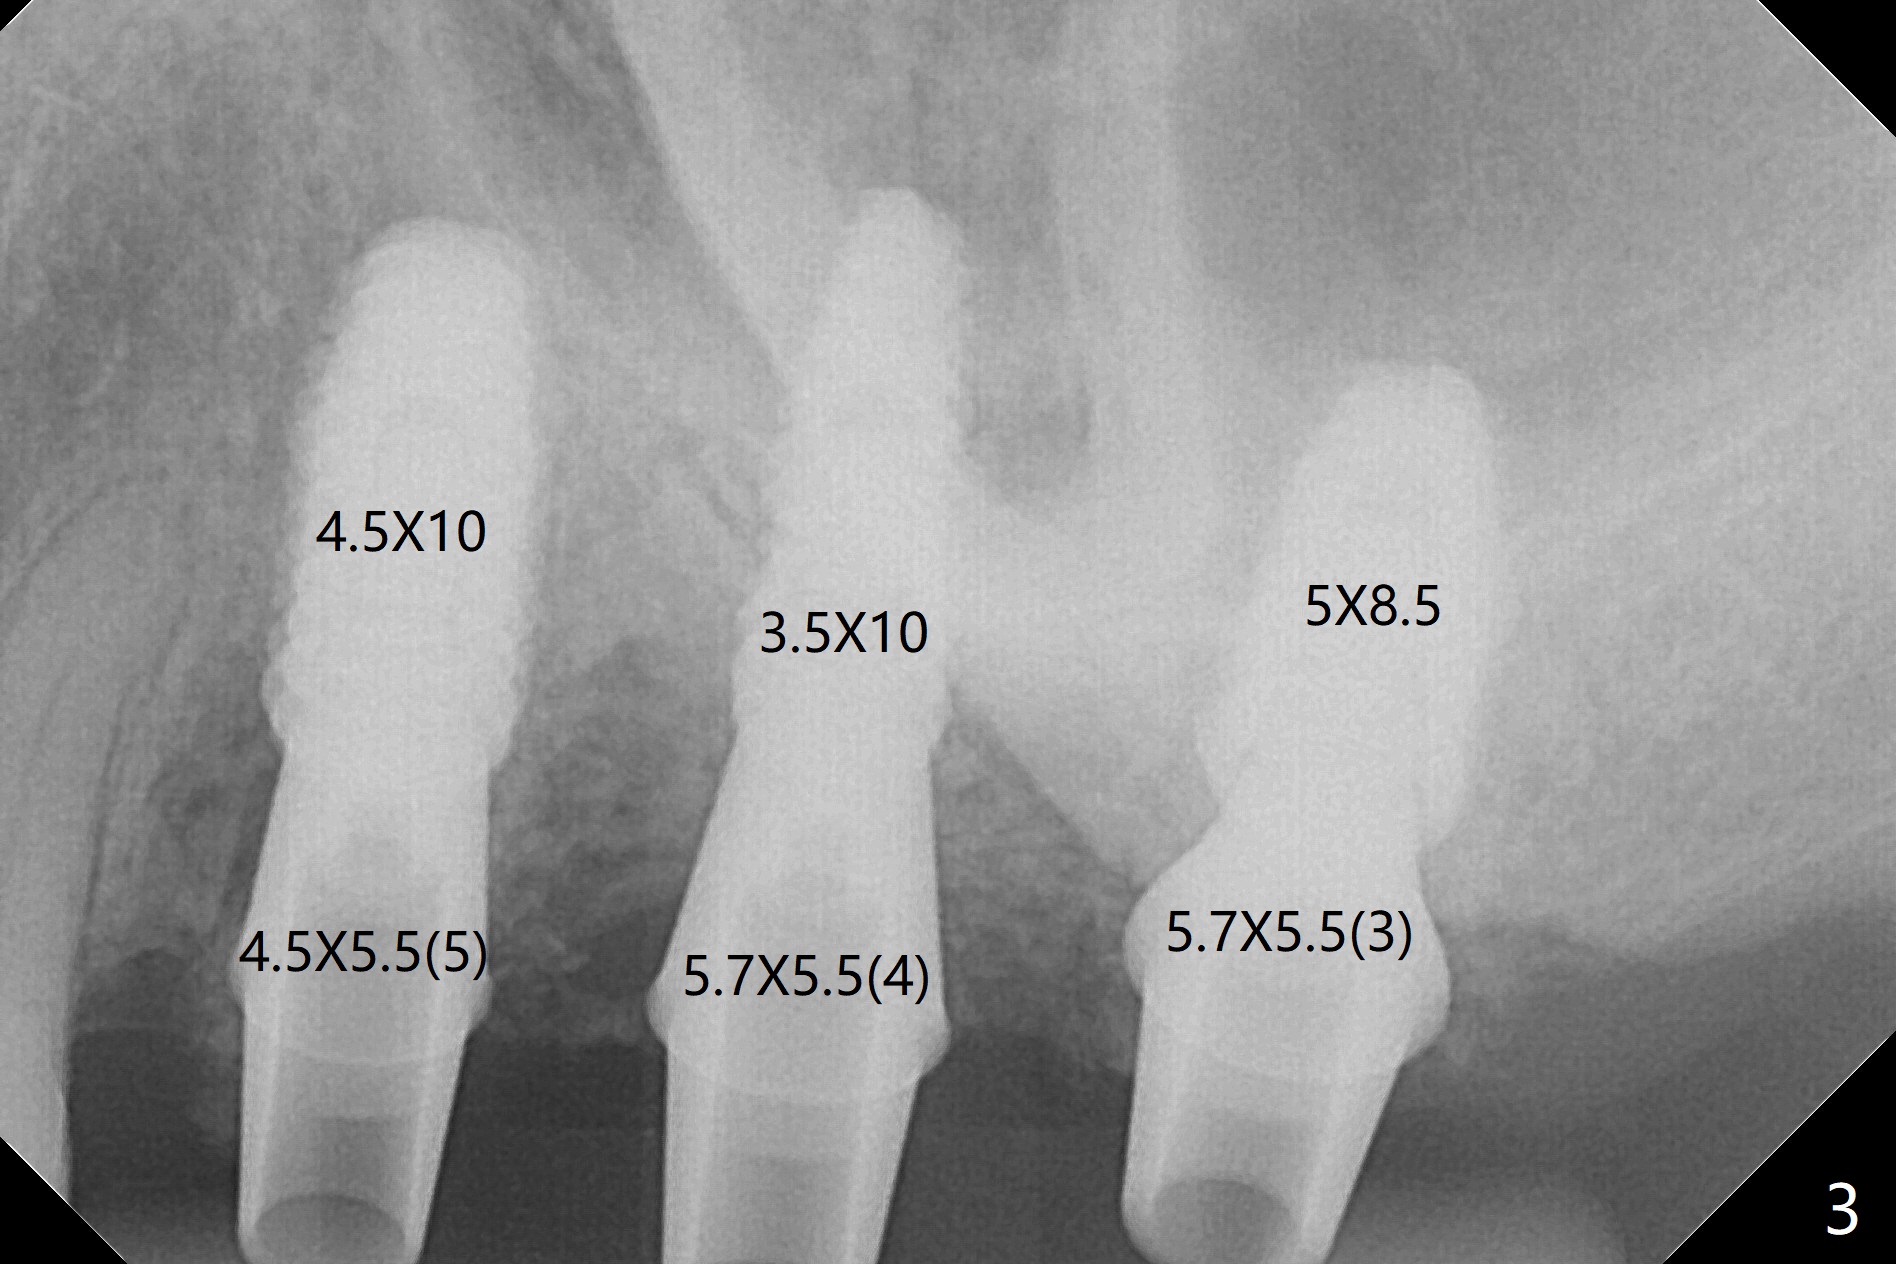

Extraction of abutment teeth associated with the loose FPD is not as easy as expected. Bony anchor placed at #14 (Fig.1 B) becomes loose while initial osteotomy a 2.2 mm drill at #13 for trajectory confirmation. The sinus membrane perforates at #15 when the sinus probe is being used. Luckily the perforation appears to be repaired with 2 pieces of PRF; sinus lift is assisted with a 4.5x10 mm dummy implant (Fig.2 *). Sinus lift at #14 is difficult and incomplete because of small osteotomy (Fig.3,5). In fact there is no sinus infection postop. Splinted immediate provisional is fabricated, but should be sectioned for individual units to form gingival scallops with distinct papillae. Three months postop, the splinted provisional is removed. The abutment at #14 is supragingival and is changed to 4.5x7(3) mm one. Individual temporary crowns are fabricated. Two weeks later, a small papilla forms between #14 and 15, while the temp at #13 is lost. The abutment at #13 changes to 4.5x7(5) mm one (Fig.7) with a new provisional, whereas those at #14 and 15 relined. In fact the abutment at #15 is incompletely seated (<) probably related to contact with the mesial crest (*). An abutment with smaller diameter and longer cuff at #15 seems to be completely seated (Fig.8,9, as compared to Fig.7). Following screw torque at 30 Ncm, impression is taken.